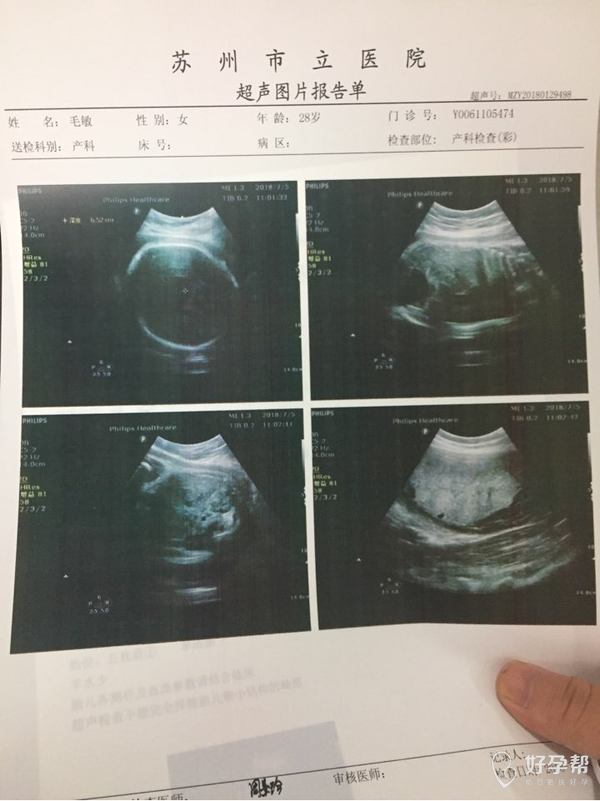

您好,根据宝宝的双顶径估计体重2630克,胎盘趋向成熟,羊水指数少。最好做个胎心监护进行评估。宝宝已经足月了,增加羊水量比较困难,可以每天有一次大量饮水约2000毫升观察看看,为了宝宝的安全,必要时适时终止妊娠。祝一切顺利,记得点击采纳。